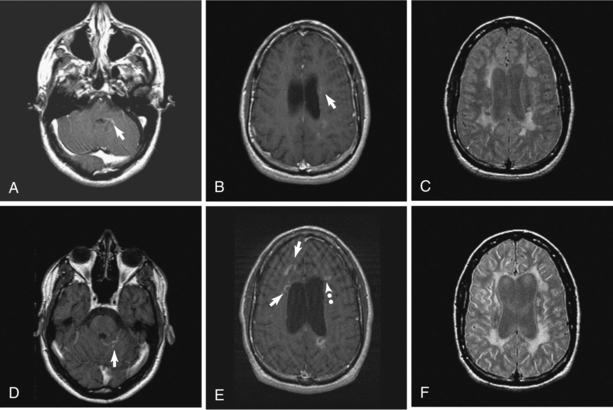

Figure 31-9 Aggressive multiple sclerosis over 2 years. Disease was initially relapsing-remitting but converted relatively quickly to secondary progressive MS. Top row: Contrast-enhanced left pons (A) and left frontal-parietal white matter (B), both showing a relatively rare edge enhancement pattern (arrows). Typical confluent T2 hyperintensities and mild-moderate volume loss based on lateral ventricle size (C). Bottom row: Two years later magnetic resonance image shows different edge-enhancing lesions (arrows) in posterior fossa (D) and both edge enhancement (arrows) and ring enhancement (dotted arrow) in deep white matter along the lateral ventricles (E). Progressive volume loss based on moderately large lateral ventricles and more extensive confluent T2 hyperintensity is seen in (F). (From Radiologic Clinics of North America, Volume 44, Number [1], January 2006. Copyright © 2006 WB Saunders Company.)

Contrast enhancement in CT and MRI suggests inflammation but is more accurately a measure of leakage of moderate-size molecules across the damaged tight junctions of the CNS endothelium. The enhancement pattern (size, shape, solid versus ring) may be variable within and more so between individuals, which reflects a heterogeneous pathology. Ring enhancement, for example, may suggest a more severe pathology. Fig. 31-10 demonstrates the development of a T2-weighted hyperintense lesion by serial MRI. The correlation between the pattern of enhancement, the underlying pathology, and the clinical course in given individuals may not be straightforward. Monitoring serial MRI studies with enhancement helps to identify agents that may be active against the early inflammatory stage of MS.170